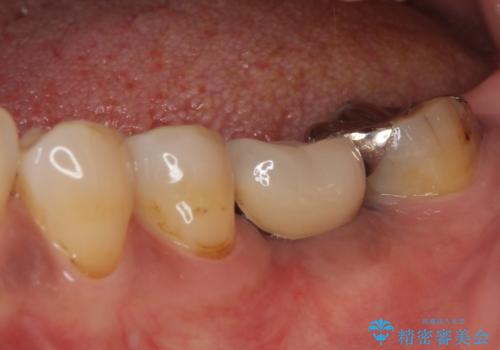

- 銀歯の装着されている奥歯がしみるとのことで来院された患者様です。

銀歯周辺の歯が欠けており、むし歯も進行している状態であったので、オールセラミッククラウンにて補綴治療を行うこととしました。